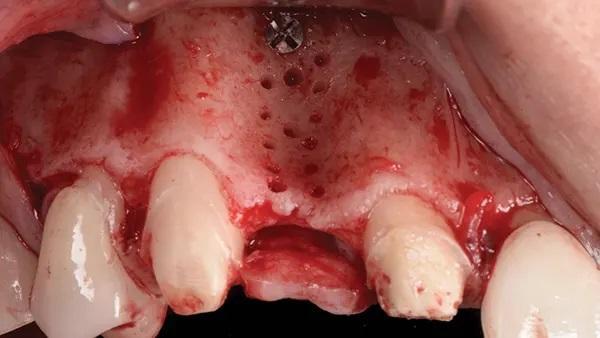

Женщина, 45 лет, с неотягощенным анамнезом, обратилась по поводу замены правого латерального резца верхней челюсти. После освобождения лоскута был выявлен сильный дефицит горизонтального гребня с остаточной шириной кости от 3 мм до 4 мм, что подтверждает данные КЛКТ (Фото 12 и Фото 13).

Фото 12: (Случай 2) Полнослойный разрез с освобождением лоскута в области угла мезиальной линии верхнечелюстного правого бокового резца и премоляра, обнажающий область клыка; обратите внимание на сильный дефицит горизонтального гребня.